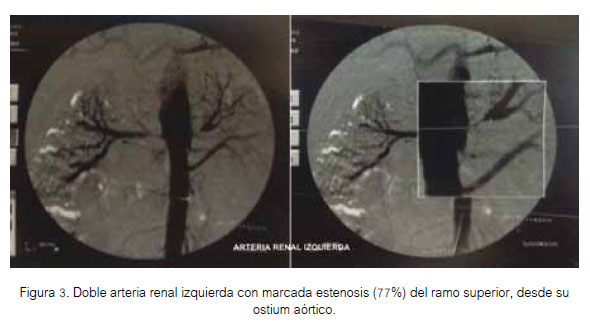

A las cinco semanas de su ingreso, se realizó arteriografía renal, que se observa en las figuras 3 y 4.